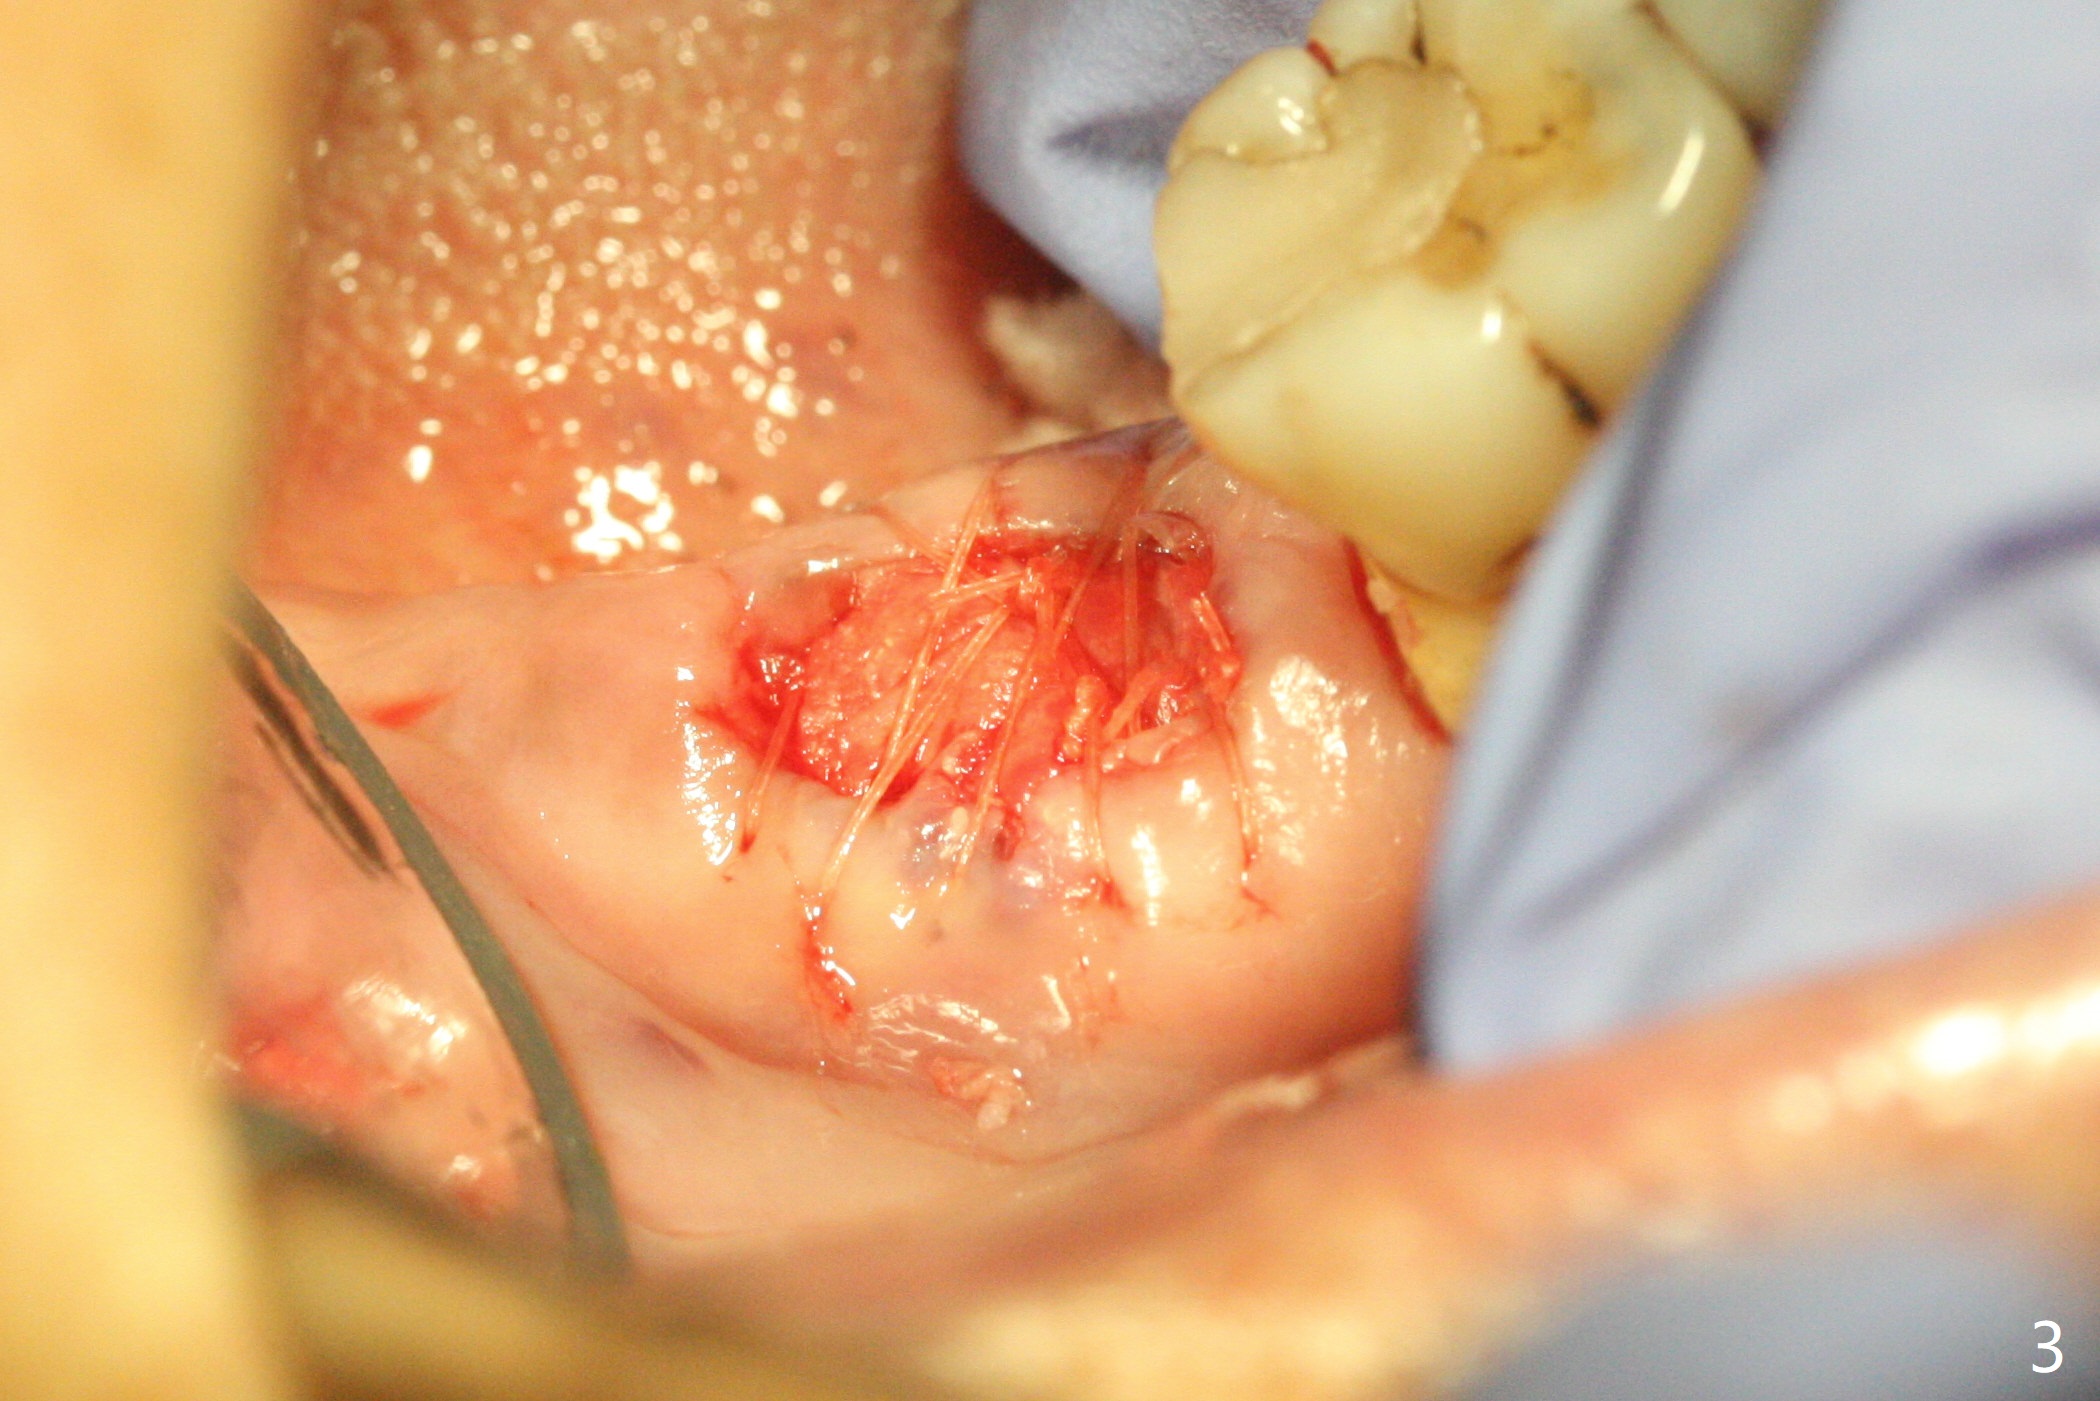

After extraction of the tooth #31 with mesial root fracture and a buccal fistula (Fig.1 <) and debride-ment, cortical: cancellous (50: 50) mineralized allograft (.5-1 mm) saturated with ~ .3 ml of .3 mg/ml of rhPDGF-BB (one component of GEM21S) is placed in the socket. Amazingly bone graft granules seem to stick to each other (semi sticky bone (Fig.2), as compared to PRF). The socket opening is covered with a piece of Osteogen plug and 12x12 mm Amnion-Chorion Allograft, followed by 4-0 PGA suture (Fig.3). The bone graft is packed as apical (Fig.4) and buccal (Fig.5 B) as possible. The patient will return to soft tissue healing check in a week. CT will be taken to determine whether the buccal plate is repaired 4 months postop. Watch Video. In fact COVIT 19 delays her return. The buccal plate seems to have reformed 7 months postop (Fig.6 >). The width and height of the ridge remains basically the same (compare Fig.7 and 8).